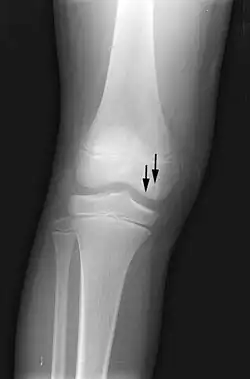

X-ray images of avascular necrosis in the early stages usually appear normal. In later stages it appears relatively more radio-opaque due to the nearby living bone becoming resorbed secondary to reactive hyperemia.[2] The necrotic bone itself does not show increased radiographic opacity, as dead bone cannot undergo bone resorption which is carried out by living osteoclasts.[2] Late radiographic signs also include a radiolucency area following the collapse of subchondral bone (crescent sign) and ringed regions of radiodensity resulting from saponification and calcification of marrow fat following medullary infarcts.